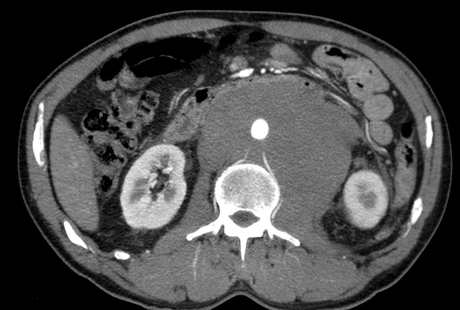

EN EL SERVICIO DE URGENCIAS SE SOLICITA ESTUDIO TOMOGRÁFICO CONTRASTADO ENCONTRANDO; MASA DE HASTA 14 CM A NIVEL RETROPERITONEAL LA CUAL ES ISODENSA A LOS MÚSCULOS PSOAS, CON ESCASA DIFERENCIACIÓN CON ELLOS. DICHA MASA PRESENTA BORDES LOBULADOS QUE SE EXTIENDE HASTA EL HILIO RENAL IZQUIERDO DESPLAZANDO EL ÓRGANO HACIA LATERAL, ENVOLVIENDO LA AORTA ABDOMINAL, LA VENA CAVA INFERIOR, ARTERIA MESENTÉRICA SUPERIOR Y AMBAS ARTERIAS RENALES SIN DISMINUCIÓN DE SU CALIBRE. TRAS LA ADMINISTRACIÓN DE MEDIO DE CONTRASTE PRESENTA UN REFORZAMIENTO HETEROGÉNEO, DE DISTRIBUCIÓN DIFUSA EN EL RESTO DEL ABDOMEN Y HUECO PELVICO SE OBSERVAN MULTIPLES IMAGENES NODULARES DE LAS MISMAS CARACTERÍSTICAS DE HASTA 1.4 CM.

EN TC MUESTRA: MASA HOMOGÉNEA BIEN DEFINIDA, CON LEVE REALCE HOMOGÉNEO CON CONTRASTE Y QUE SE EXTIENDE ENTRE LAS ESTRUCTURAS NORMALES RETROPERITONEALES SIN COMPRIMIRLAS. LA AORTA Y VCI PUEDEN SER DESPLAZADAS ANTERIORMENTE PRODUCIENDO EL “SIGNO DE LA AORTA FLOTANTE”. LAS CALCIFICACIONES Y NECROSIS NO SON FRECUENTES ANTES DE LA ADMINISTRACIÓN DEL TRATAMIENTO.

MASCULINO DE 56 AÑOS CON MASA EN EPIGASTRIO A QUIEN SE LE REALIZA USG Y TAC CONTRASTADA MOSTRANDO MASA RETROPERITONEAL DE HASTA 14 CM, LA CUAL DESPLAZA LAS ESTRUCTURAS VASCULARES.